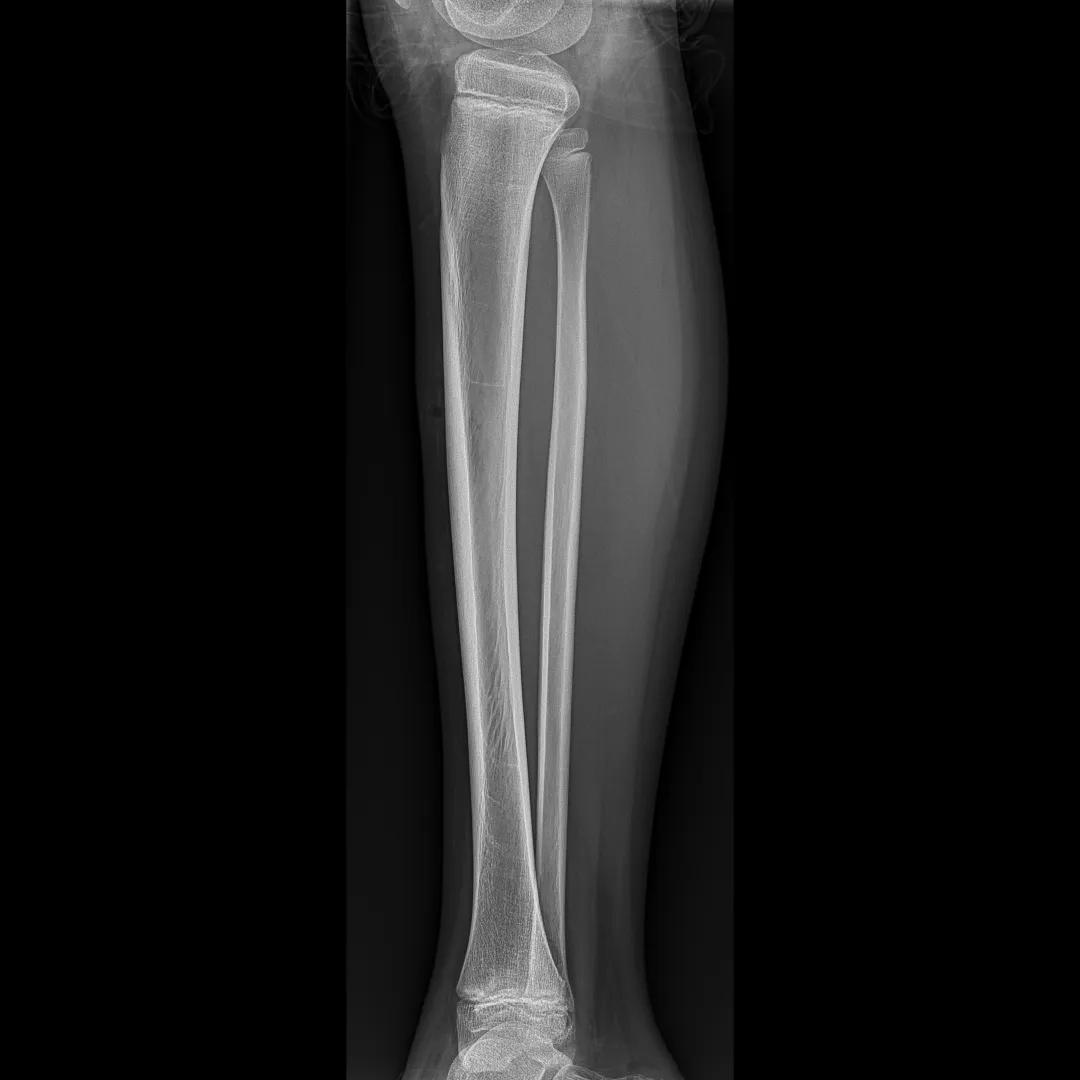

最后来看看“飞燕”的临床成像:

滑动查看更多图片